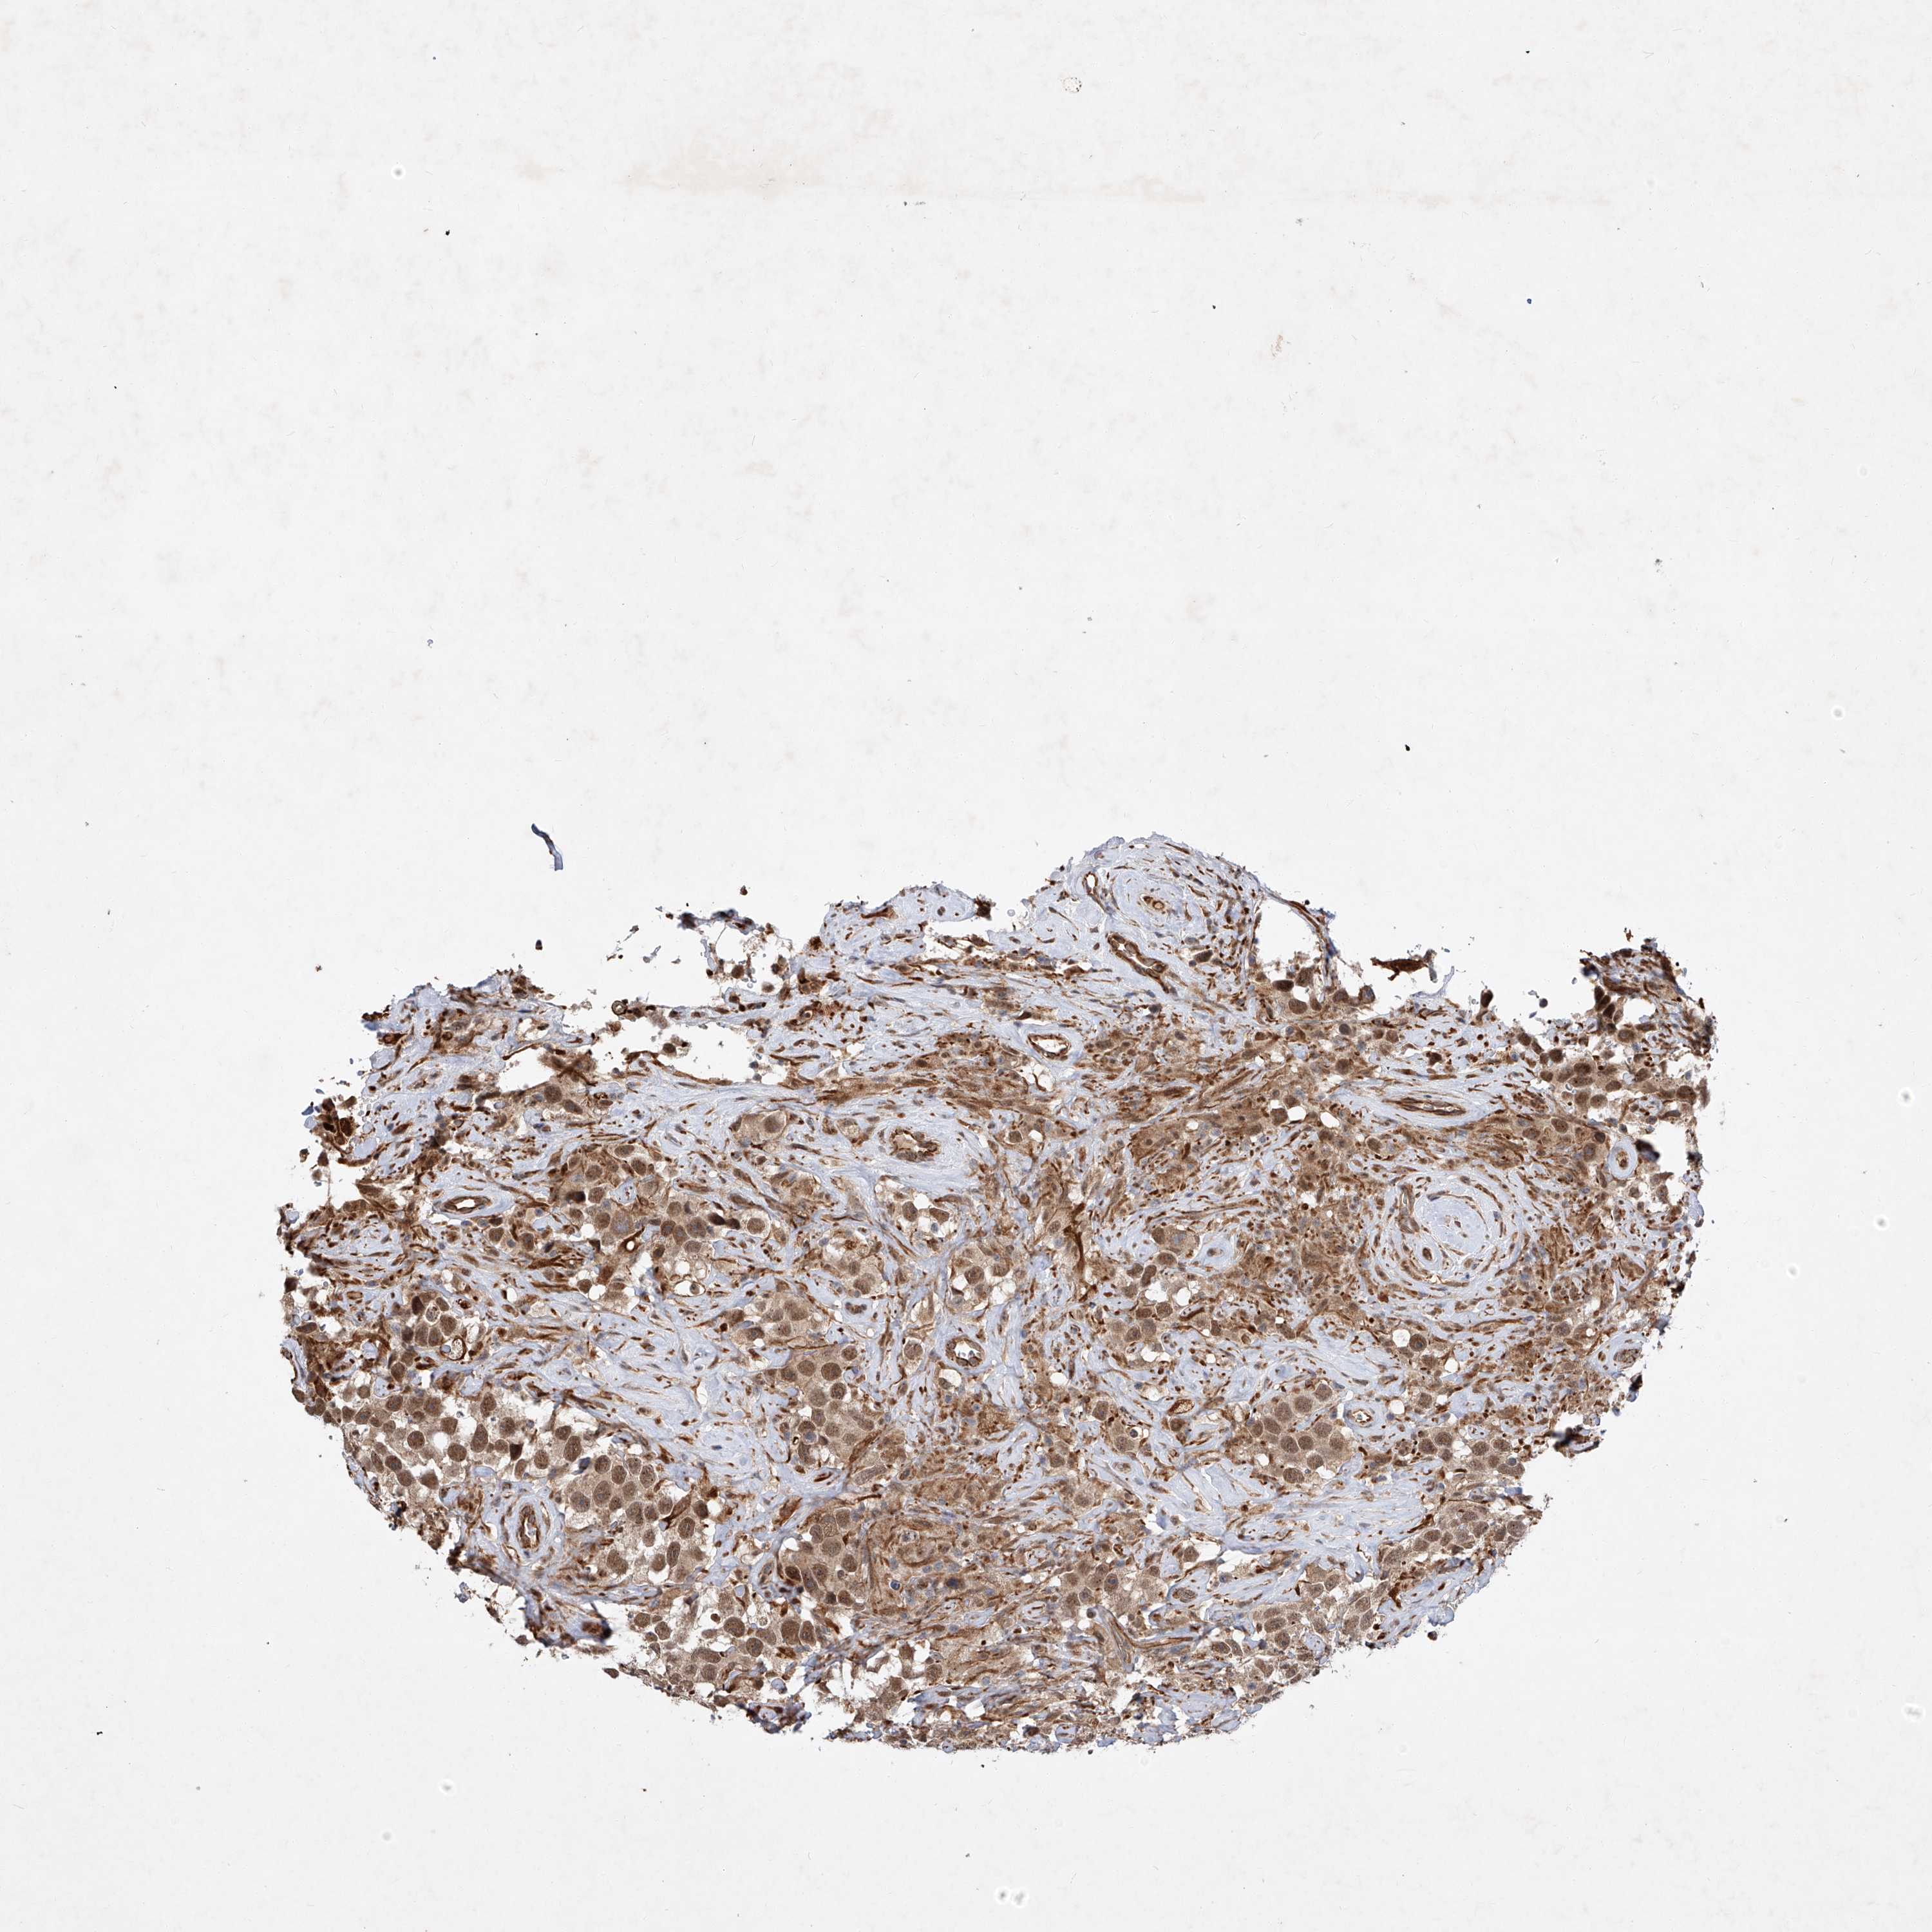

TESTIS CANCER - Protein expressioni

A mouse-over function shows sample information and annotation data. Click on an image to view it in a full screen mode. Samples can be filtered based on level of antibody staining by selecting one or several of the following categories: high, medium, low and not detected. The assay and annotation is described here.

Note that samples used for immunohistochemistry by the Human Protein Atlas do not correspond to samples in the TCGA dataset.

Antibody stainingi

Antibody staining in the annotated cell types in the current human tissue is reported as not detected, low, medium, or high, based on conventional immunohistochemistry profiling in selected tissues. This score is based on the combination of the staining intensity and fraction of stained cells.

Each image is clickable and will lead to virtual microscopy that enables deeper exploration of all samples and also displays staining intensity scores, fraction scores and subcellular localization as well as patient and tissue information for each sample.

Antibody HPA029281

Antibody HPA029282

Staining

High

Medium

Low

Not detected

Intensity

Strong

Moderate

Weak

Negative

Quantity

>75%

75%-25%

<25%

None

Location

Nuclear

Cytoplasmic/membranous

Cytoplasmic/membranous,nuclear

Carcinoma, Embryonal, NOS

Seminoma, NOS

Urothelial carcinoma, High grade